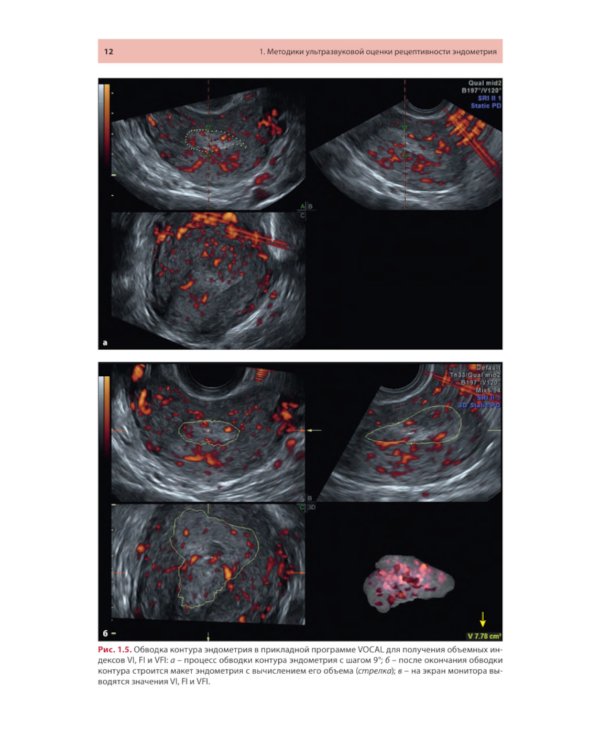

Методические рекомендации освещают современное состояние проблемы ультразвуковой оценки рецептивности эндометрия от общепринятых маркеров до малоизученных, в том числе перспективных, направлений. Описаны ультразвуковые методики, позволяющие оценивать признаки рецептивности в 2D- и 3D-режимах с акцентом на ошибках, которые влияют на интерпретацию результатов. Представлены различные шкалы комплексного анализа. Утверждено в качестве методических рекомендаций для проведения циклов тематического усовершенствования «Ультразвуковая диагностика в гинекологии», общего усовершенствования, ординаторов и аспирантов, проходящих обучение по направлению «Ультразвуковая диагностика, акушерство и гинекология, репродуктология». Протокол Ученого совета ФНМО МИ ФГАОУ ВО РУДН №5 от 16.05.2023.| Издательство | МЕДпресс-информ |